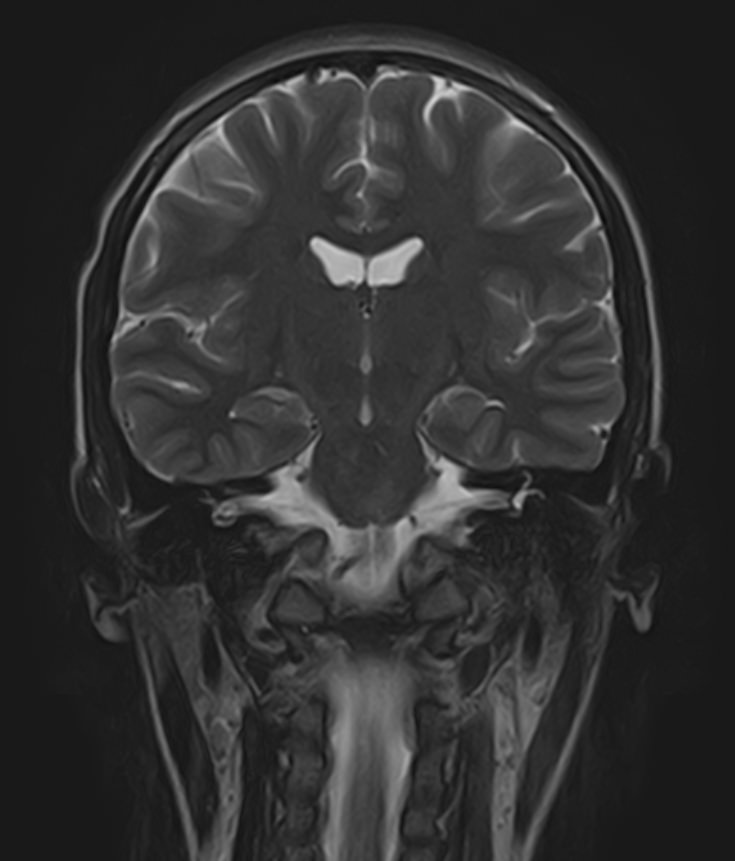

В клинике «Доступная медицина» можно пройти комплексное обследование, включающее в себя несколько протоколов сканирования близко расположенных друг от друга анатомических областей – шейного отдела позвоночника и головного мозга. Метод комплексного обследования оценивает состояние всех структур головного мозга и шейного отдела позвоночника. При этом дополнительные протоколы обследования позволяют визуализировать крупные сосуды шеи и сосудистую сеть головного мозга.

Сканирование проводится на современном высокопольном магнитно-резонансном томографе закрытого типа TOSHIBA VANTAGE TITAN 1,5 Тесла. Магнитно-резонансный томограф производит послойное сканирование исследуемой зоны в разных плоскостях, затем при помощи компьютерных программ преобразует полученные данные в трехмерные изображения. При этом кровеносная система реконструируется как вместе с окружающими тканями, так и отдельно без них.

Что показывает МРТ головного мозга + МРТ шейного отдела позвоночника + МР-ангиография шеи и головного мозга

В рамках проведения данного комплексного исследования можно выявить:

• очаги ишемического и геморрагического инсульта, область поражения, признаки отека головного мозга, стадию развития заболевания;

• доброкачественные и злокачественные новообразования, их точную локализацию, стадию развития процесса, проводить динамическое наблюдение за опухолевым процессом на фоне лечения;

• признаки демиелинизирующих заболеваний (рассеянный склероз), выявить очаги поражения миелиновой оболочки нервных волокон, определить стадию заболевания;

• характерные признаки дегенеративных заболеваний головного мозга (болезнь Альцгеймера, старческая деменция, болезнь Паркинсона), определить изменения коры головного мозга и подкорковых структур;

• поражение структур головного мозга на фоне травм, гематомы головного мозга;

• изменения, характерные для психических расстройств различного генеза (эндогенных и экзогенных), после вирусных инфекций, черепно-мозговых травм, отравлений токсическими веществами, на фоне наследственных заболеваний;

• участки сужения, извитость, образование петель и перегибов сосудов;

• нарушения оттока крови за счет тромбообразования в венозном русле;

• ангиомы, сосудистые мальформации;

• остеохондроз, спондилоартроз, спондилез, межпозвонковые грыжи, унковертебральный артроз, сколиоз, усиленный или выпрямленный лордоз как нарушение статической функции позвоночника, травмы, аномалии позвоночника.